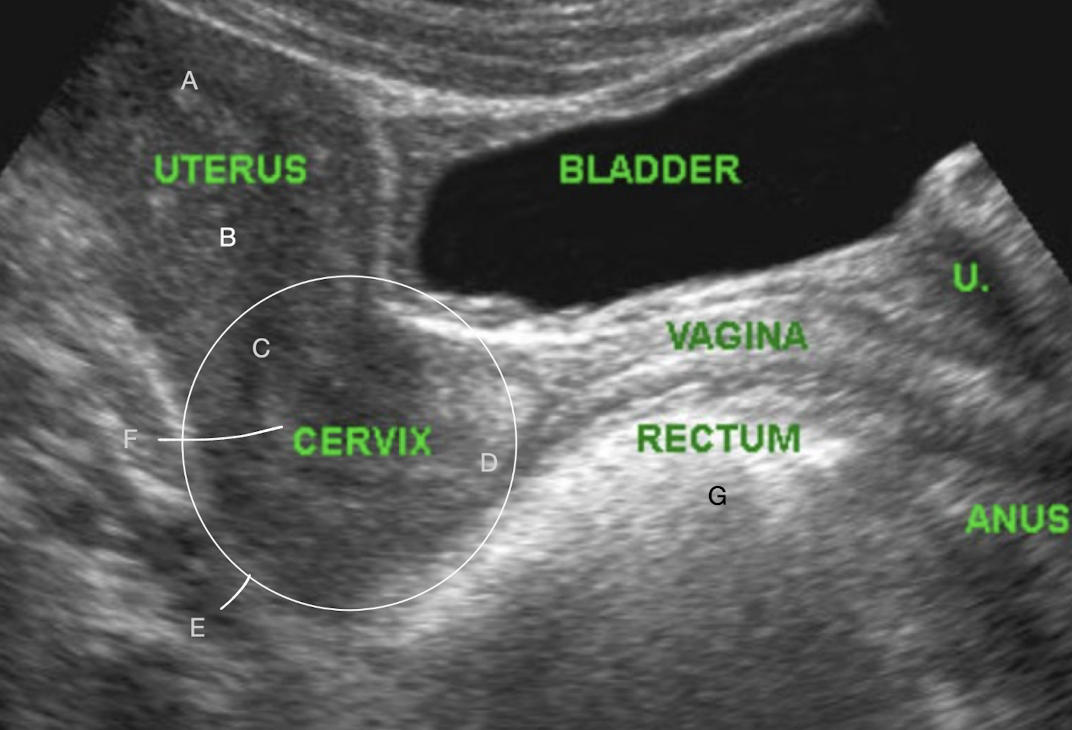

A?

fundus

B?

body

C?

internal os

D?

external os

E?

LUS

F?

cervical canal

G?

bowel

transvaginal pelvic anatomy in LONG